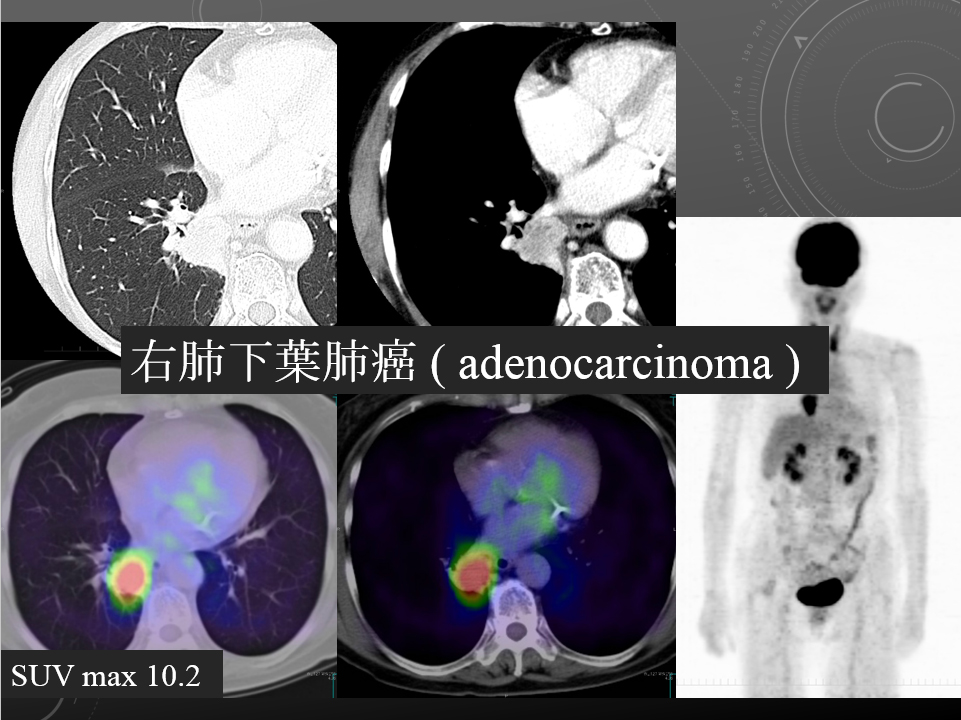

68F CEA 高値精査。消化器内科依頼。既往に脳梗塞、心筋梗塞、胃ポリープあり。

右肺下葉腺癌。

右肺下葉の縦隔側には最大径31mm大の不整形な腫瘤性病変を認めます。表面には部分的にspicula所見が見られ、胸膜に広汎に隣接するように存在しています。内部は辺縁を中心に淡い造影効果を呈しています。原発性肺癌病巣が疑われます。肺門部にはリンパ節腫大像が見られますが、縦隔領域に明らかに有意なリンパ節腫大は指摘出来ません。

左肺下葉に末梢側には淡い濃度上昇所見が見られ、GGO病変が疑われます。この他、肺野に明らかな腫瘤性病変は指摘できません。

肝内に占拠性病変は認められません。

明らかな副腎腫瘤は指摘できません。

両腎には嚢胞と考える低吸収像を認めます。

胸腹水貯留は見られません。

腹壁瘢痕ヘルニア所見を認めますが、明らかな腸管の逸脱は見られません。

・Lung cancer s/o

SUVmaxは10.2

右肺下葉内側の腫瘤に一致して異常集積を認める。

右肺下葉原発性肺癌 ( adenocarcinoma )

右肺下葉原発性肺癌 ( adenocarcinoma )